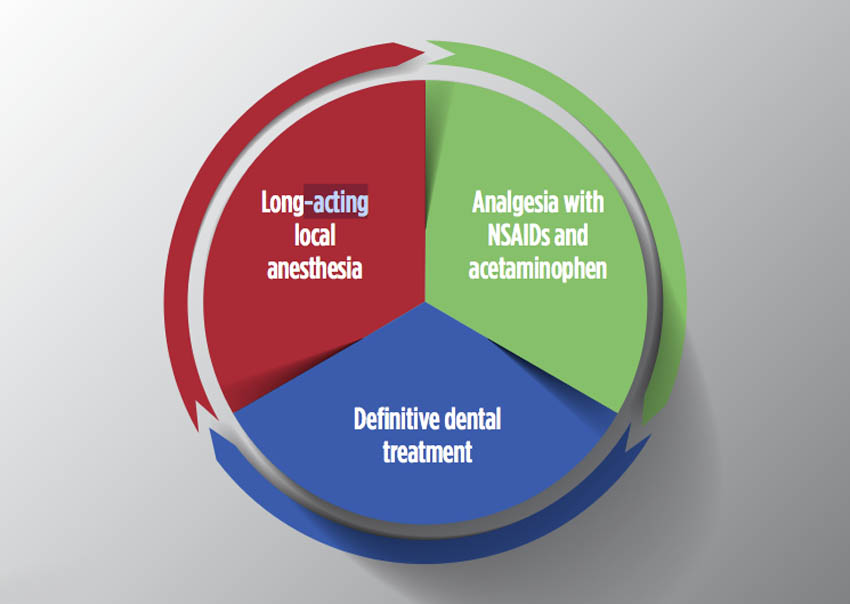

Μία ενδελεχής κατανόηση της γένεσης του πόνου μπορεί να επιτρέψει στους κλινικούς να αντιμετωπίσουν με αποτελεσματικό τρόπο τον πόνο των ασθενών τους, χρησιμοποιώντας στρατηγικές οι οποίες βασίζονται στην τεκμηρίωση. Η διενέργεια της κατάλληλης τοπικής αναισθησίας και η παροχή λεπτομερών οδηγιών σχετικά με τη συνδυασμένη χρήση ιβουπροφαίνης και ακεταμινοφαίνης προσφέρουν αποτελεσματικές στρατηγικές για τον οδοντίατρο ο οποίος αναλαμβάνει το καθήκον της διαχείρισης του οξέος οδοντικού πόνου. Οι στρατηγικές αυτές συνοψίζονται στην Εικ. 6. Η παρατεθείσα στο παρόν άρθρο έρευνα υποδεικνύει τη χρήση 400 mg ιβουπροφαίνης σε συνδυασμό με 500 mg ακεταμινοφαίνης ως τη στρατηγική πρώτης γραμμής για την αντιμετώπιση του οδοντικού πόνου, είτε πρόκειται για προεγχειρητικό ή για μετεγχειρητικό πόνο. Εάν αυτός ο συνδυασμός αποδειχθεί ανεπαρκής, έχει δειχθεί ότι η αύξηση της δοσολογίας στα 800 mg ιβουπροφαίνης παρέχει τη μέγιστη δράση ανακούφισης του πόνου σε σύγκριση με άλλα διαθέσιμα συνταγογραφούμενα και μη συνταγογραφούμενα αναλγητικά που λαμβάνονται από το στόμα. Τα τοπικά αναισθητικά μπορούν να εξυπηρετήσουν ως ένα πολύτιμο συμπλήρωμα ή ακόμη και υποκατάστατο των αναλγητικών από το στόμα, παρέχοντας στοχευμένη και πλήρη ανακούφιση από τον πόνο στις περισσότερες περιπτώσεις, τόσο πριν την οριστική οδοντιατρική θεραπεία όσο και μετά από αυτήν.

Αναισθησία μακράς δράσης

Αναλγησία με ΜΣΑΦ και ακεταμινοφαίνη

Οριστική οδοντιατρική θεραπεία